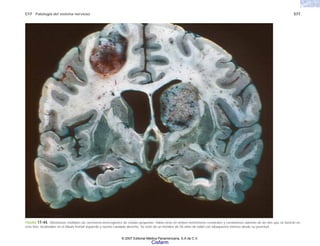

Cisfarm

C8 Patología general de las neoplasias 155